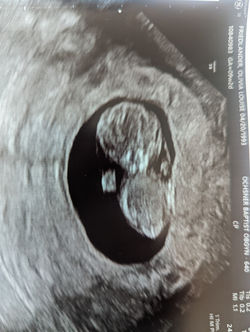

![]() GREMLINMichael special requested they print us some of the more "horror movie" scans. | ![]() Lil hand!All five-ish fingers! |